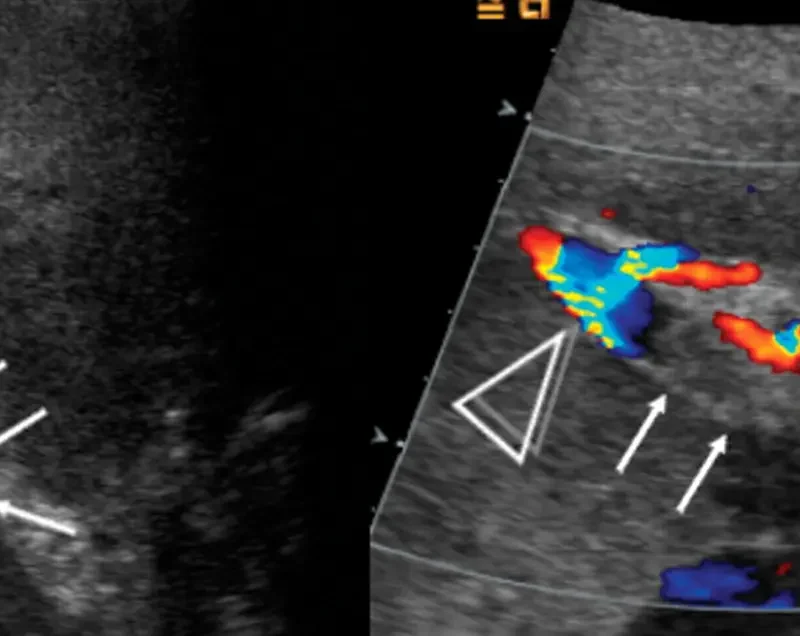

- Ultrasound Signs of Budd-Chiari Syndrome: An Essential Diagnostic Tool